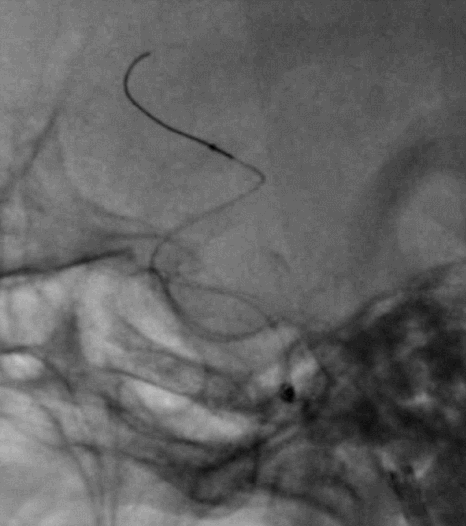

Cat5完全释放支架后,拉推送杆后支架近端打开,后将Cat5跟进血流导向装置内尝试“按摩”,支架整体贴壁不够理想。

Cat5通过后海绵窦段狭窄即较前改善

Cat5提供稳定通路,引入3.5mm×10mmHiryu球囊扩张由远端及近端扩张狭窄段及支架贴壁欠佳处

造影示狭窄及贴壁较前进一步改善

导丝成袢,继续“按摩”改善贴壁

“按摩”后再次造影,C2段狭窄仍较明显且贴壁欠佳

再次引入球囊扩张近端

扩张后再次复查造影示支架打开及贴壁较前明显改善